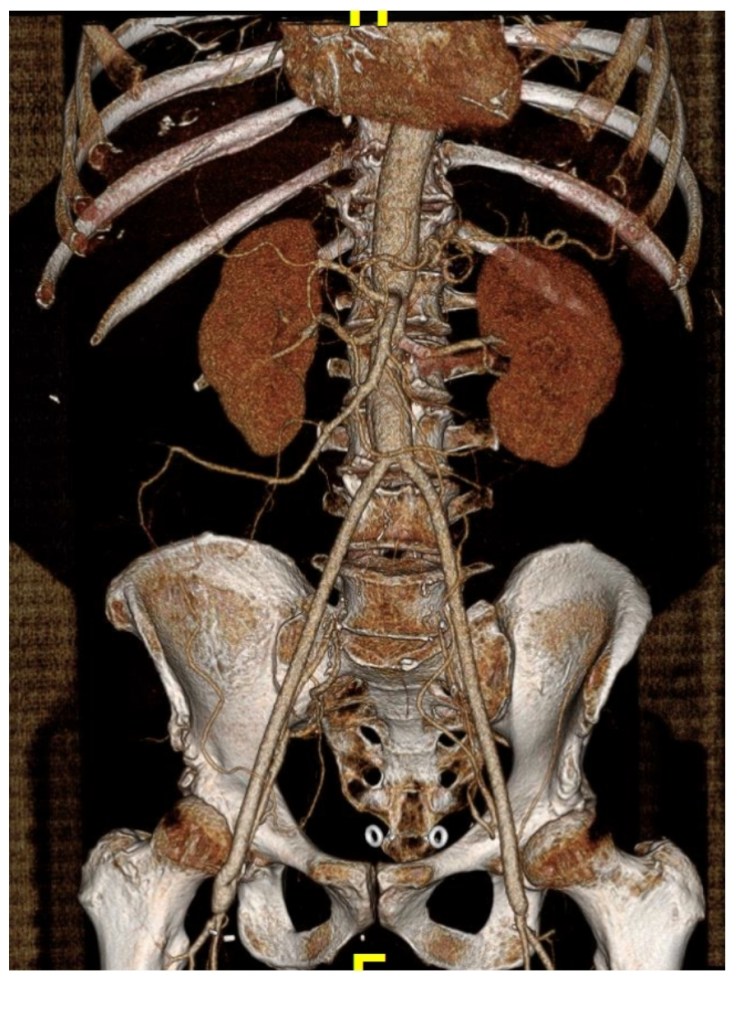

Take for example this patient below with Leriche syndrome with a triad of smoking, claudication, and impotence.

Because of his relative youth, being his 50’s, I felt the most appropriate procedure was an aortobifemoral bypass.

The only real complexity to manage was the severe stenosis he had in his left renal artery.

The patient recovered and was discharged on POD#6 with normal renal function. In followup, his CTA showed excellent graft and stent patency.